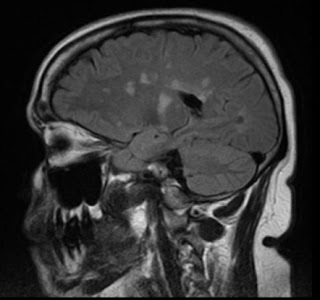

Esclerose Múltipla

A Esclerose Múltipla é uma patologia inflamatória crônica do Sistema Nervoso Central, acometendo desta forma o Encéfalo e a Medula Espinhal, de etiologia auto-imune.